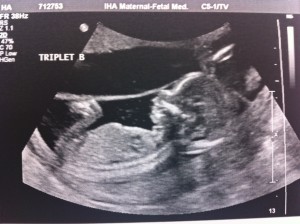

Hello!! I’m 16 weeks today and it was the BIG appointment where we learned the sex of the fetuses!!

Baby A – is a BOY!

Baby B – is a GIRL!

Baby C – is a BOY!

A is 170 grams, B is 175 grams and C is 178 grams so they’re all measuring well. Grow, grow, grow!